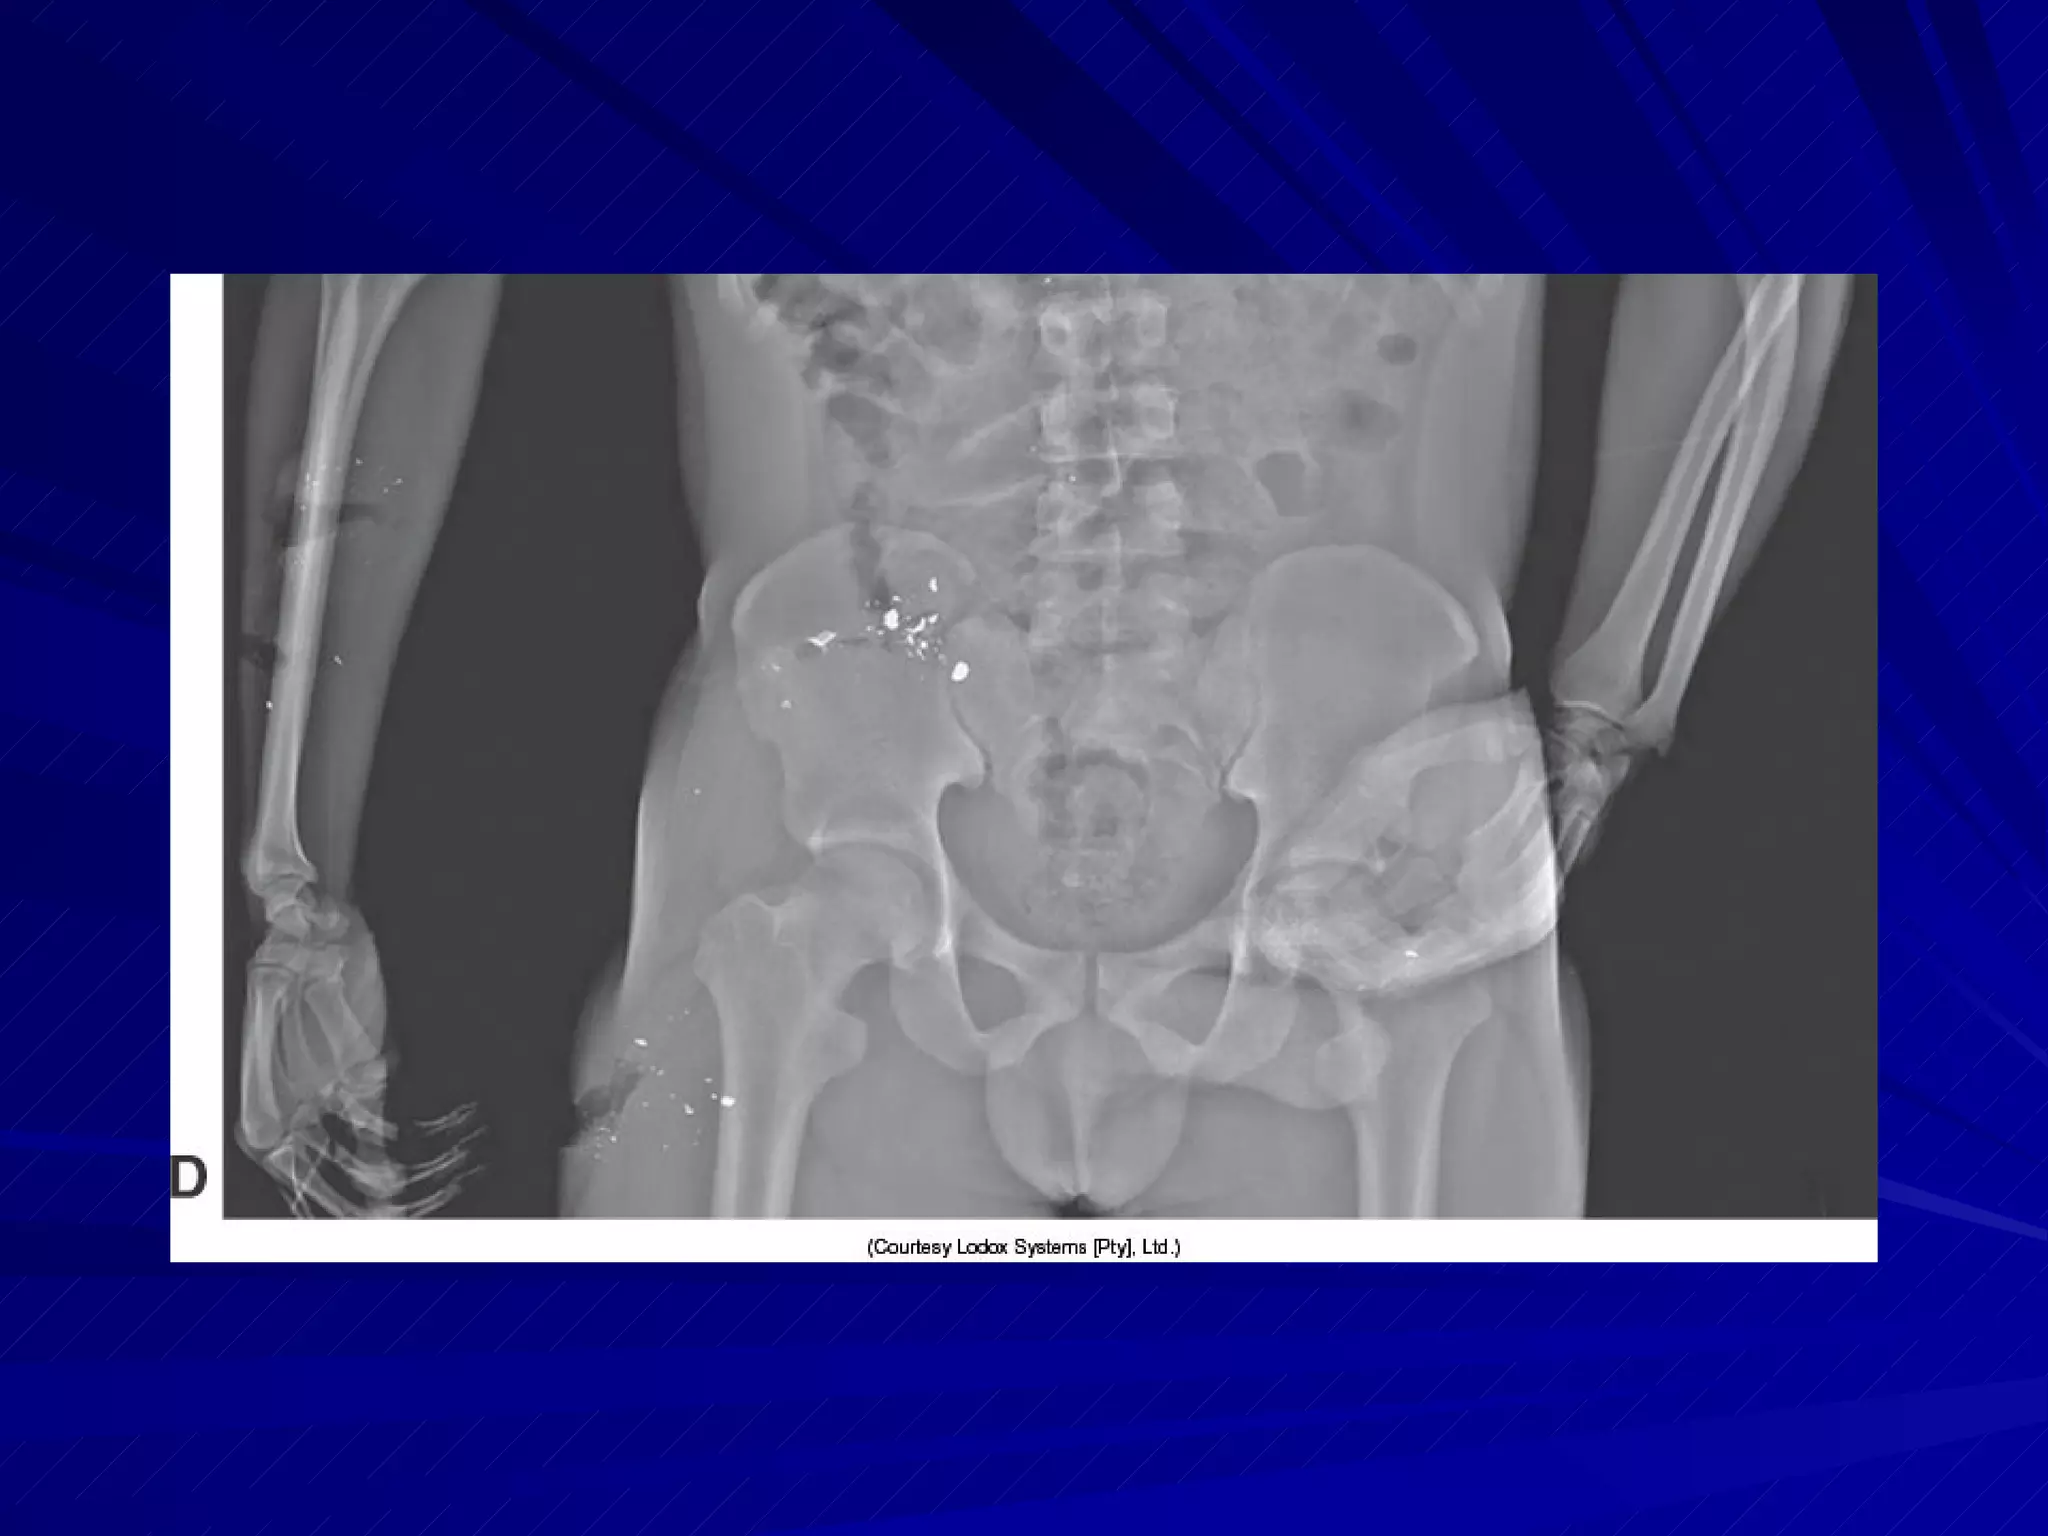

Preliminary Considerations Specialized trauma imaging systems reduce the amount of time required to obtain diagnostic images One type provides greater flexibility in IR/CR maneuverability Another type scans the entire body in a few seconds

Preliminary Considerations Specializedtrauma imaging systems reduce the amount of time required to obtain diagnostic images One type provides greater flexibility in IR/CR maneuverability Another type scans the entire body in a few seconds

ID Markers Rightor left side markers must be included on each image Other required ID markers must be in the blocker or elsewhere on the final image Markers used for penetrating trauma to identify entrance and exit wounds

Abdomen Mark entranceand exit wounds, if present Align shoulders and hips in same plane MCP parallel to table CR perpendicular to center of IR Image demonstrates entire abdomen with pubic symphysis visible at lower border